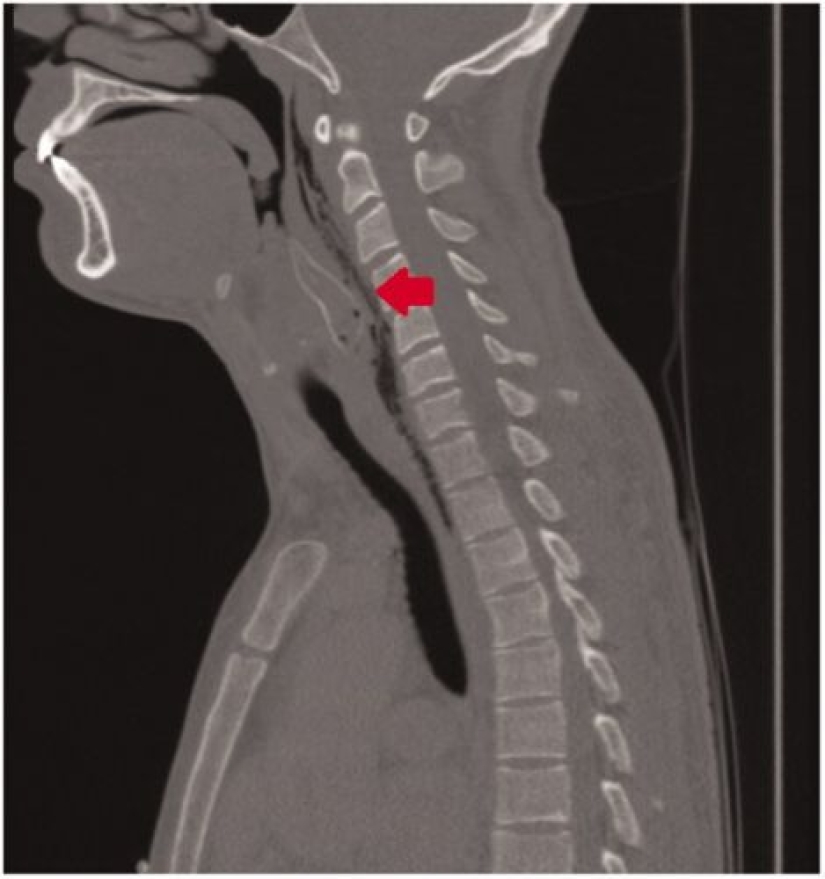

A couple of hours later, when all the artisanal methods were tried, friends took the joker to the nearest clinic. The strange patient did not want to explain to the doctors what was the reason for his plight and simply complained that he choked on food. But the X-ray immediately showed that there was a fish inside the guy and he had to admit to performing a stupid trick.

Why did this situation arise, which almost cost a young man his life? It turns out that harmless-looking golden catfish (bronze corydoras), in their natural habitat, have a bad reputation among predators. Behind the fins of these fish are sharp hard spikes, which they, in case of danger, lift up straight. Ideally, this should prevent a large fish from swallowing a baby. But man is arranged somewhat differently and the spikes detained the catfish where neither he nor his victim could do anything.